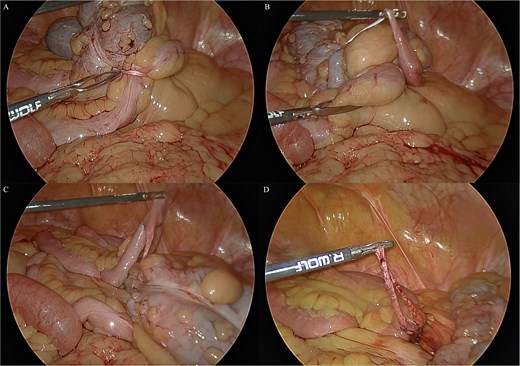

She underwent a diagnostic laparoscopy which identified a partial caecal obstruction secondary to a fibrous band running from a Meckel’s diverticulum around the caecal pole to the small bowel mesentery (Fig. 2). It did not have the typical appearance of a mesodiverticular band and was thought to have been a band running from the MD to the umbilicus which had been let down from the umbilicus at her previous laparotomy and subsequently implanted itself in the small bowel mesentery. The band was untwisted from around the caecum. Simple diverticulectomy of the MD and its band was performed. The patient recovered uneventfully. She was subsequently seen in the out-patient clinic and reported resolution of her symptoms.

Intraoperative laparoscopic views. (A) The band is seen wrapped around the caecum causing the partial obstruction. (B) The band is untwisted from around the caecum and the Meckel’s diverticulum is revealed. (C) The Meckel’s diverticulum and its band are examined. (D) The band is transected.